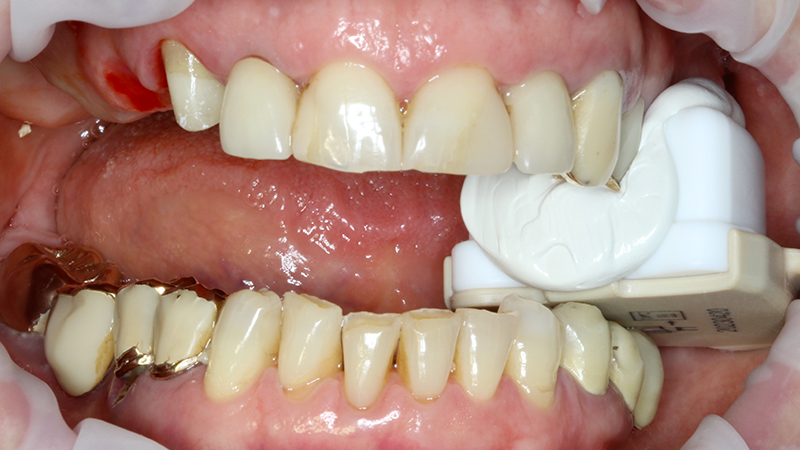

La finalizzazione del caso avveniva con protesi in metallo-ceramica passivata su cappe conometriche in bocca (Figs. 24, 25, 26, 27, 28, 29, 30, 31, 32) e radiografie finali ad un anno dal carico (Figs. 33, 34).

Applicazione ponte 17-14 in metallo ceramica su cappette conometriche passivate in bocca mediante cemento

Fig. 24 - Applicazione ponte in metallo ceramica su cappette conometriche passivate in bocca mediante cemento Multilink Hybrid e risultato finale

Applicazione ponte 17 - 14 in metallo ceramica su cappette conometriche passivate in bocca mediante cemento Multilink Hybrid e risultato finale

Fig. 25 - Applicazione ponte 17 - 14 in metallo ceramica su cappette conometriche passivate in bocca mediante cemento Multilink Hybrid e risultato finale